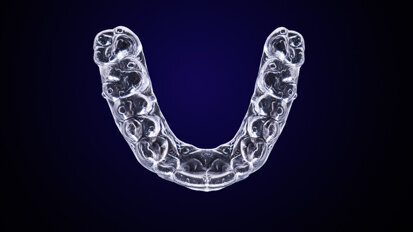

Investors bet on orthodontist-led digital clear aligner therapy

HONG KONG, China: Recent developments in Hong Kong have shown support for both sides of the debate surrounding clear aligner treatment. The Chinese ...

save